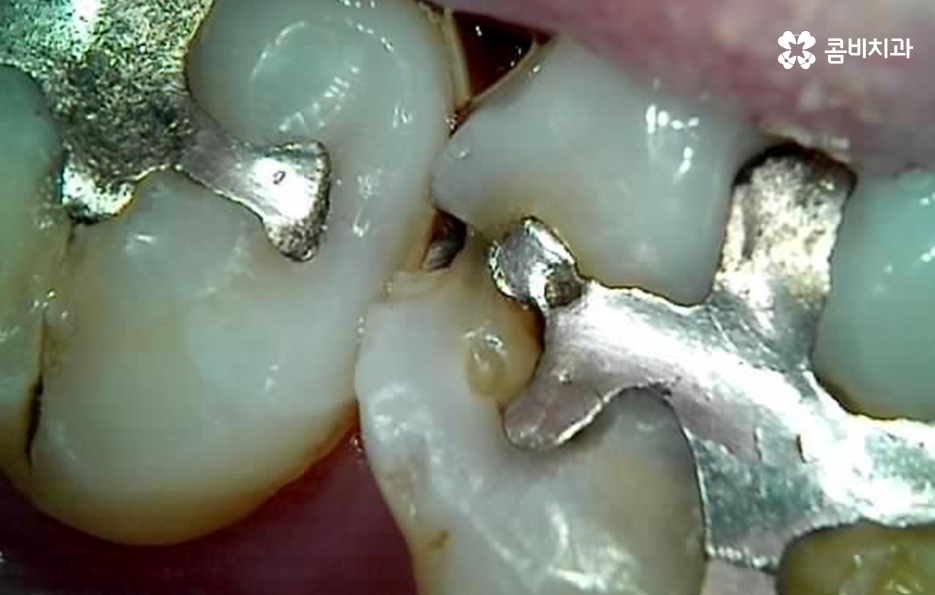

오늘은 자연치아를 결국 잃게 되면 대표적인 사례 중에서 오래된 보철물 혹은 보철물 관리가 잘 안되어 결국 발치로 이어지는 사례에 대해서 알아볼 거예요. 오래된 보철물 속에서 진행되는 2차 충치는 알아차리기도 쉽지 않고 이미 깊어지면 치아 뿌리 쪽으로 충치가 진행되어 발치로 이어지는 경우가 많다는 점에서 보철물 관리의 중요성에 대해서 재인식하는 포스팅이 되길 바라고 있어요

보통 어금니 크라운을 씌운 경우에는 신경치료를 한 후에 크라운을 씌운 경우가 많기 때문에 이미 크라운 속에 충치가 심하게 진행되어도 통증과 같은 증상으로 문제를 잘 못느끼는 경우가 많이 있는데요

치아 문제에 대해서 안아프면 별 문제 없겠지 하고 잘 지내고 있다가 예전에 씌워서 기억도 잘 안나는 크라운이 흔들리거나 냄새, 잇몸 염증 등이 발생하여 치과를 찾게 되었는데 이미 심각한 수준으로 치아 내부에 충치가 진행되어 결국 발치에 이르게 되는 경우가 많이 있어요

이러한 보철물 속 2차 충치가 발생된 경우에는 환자분의 입장에서도 그동안 잘 쓰던 치아라고 생각했다가 당황하는 경우도 많고 한편으로는 치아를 뽑고 임플란트를 해야하는지 걱정하는 분들이 많을 거예요

크라운 혹은 오래된 보철물 내부에 2차 충치가 발생된 경우에 자연치아를 보존할 수 있는지에 대한 판단은 엑스레이 만으로 진단할 수 있는 문제는 아니며 치아 내부에 충치가 어느정도나 진행되었고 잔존하는 치아의 양이 어느정도나 되는지에 따라서 발치 혹은 치아 보존 치료에 대한 판단을 할 수 있어요

이미 신경치료를 했던 치아라고 해도 보철물 제거 후에 충치를 잘 치료하고 재신경치료를 통해서 치아를 보존할 수 있는 경우가 있고 발치 후 임플란트를 해야하는 경우도 있는데요

이러한 판단 기준은 치아 내부에서 충치가 발생되었을 때 충치가 얼마나 치아 뿌리 쪽으로 깊어졌는지 혹은 살릴 수 있는 치아가 얼마나 잔존하는지에 따라서 다르며 치과의사 역시도 치아 속을 확인해보고 충치를 제거해봐야 알기 때문에 치과의사의 숙련도, 경험도 중요하겠지만 치과의 내원 시점이 무척이나 중요하기 때문에 보철물이 오래된 경우에는 꼭 주기적으로 치과 검진을 하시고 의사의 소견 하에 크라운의 교체가 필요하다면 문제가 커지기 전에 재치료를 적절히 받는 것이 자연치아 보존에 중요할 거예요